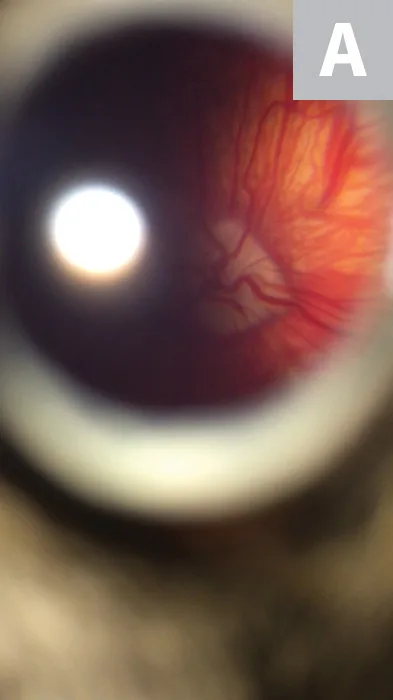

FIGURE 1

A miniature schnauzer presented for red eye. This representative image of poor photographic technique was taken from a close working distance, but shadowing obscures details of the ocular surface from being perceived.

Shadowing and underexposure of the ocular surface and intraocular structures are common problems with smartphone photography, often yielding images of poor diagnostic quality (Figure 1). Close working distances, delayed flash, and patient movements all make smartphone flash photography of the eye difficult. These obstacles can be overcome and shadowing and underexposure avoided by enabling the continuous flash in the camera’s video mode (see Continuous Flash Technique). When capturing images in this manner, it is often helpful to direct light into the pupil so a fundic/tapetal reflection is generated (Figure 2). External illumination (eg, overhead surgical lamp, transilluminator, penlight) can also be used to reduce shadowing of the eye (Figure 3).